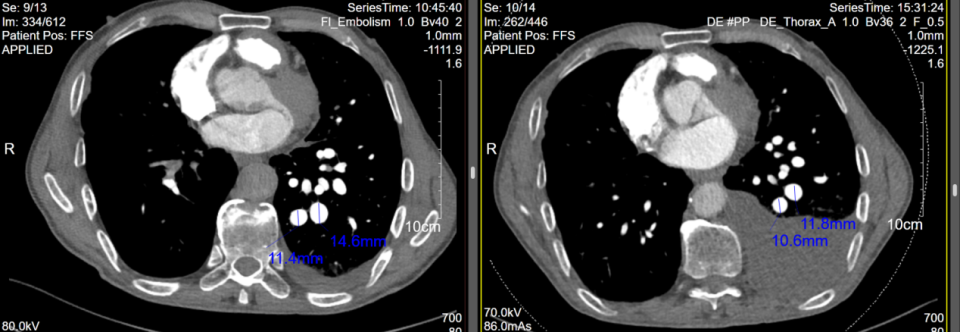

患者于2025年9月15日行右心导管检查+超选择性肺动脉造影+肺动脉分支球囊扩张术+肺动脉支架植入术。术中测肺动脉压力 46/11 (23) mmHg,热稀释法测量心输出量约3.0L/min,肺血管阻力6 Wood单位。超选择性肺动脉造影提示多支肺动脉狭窄闭塞,右侧A8-A10肺动脉共干狭窄90%以上,狭窄部位最大扩张直径为6mm,植入10 x 40 mm支架1枚后因狭窄严重,支架缩入远端,后植入10 x 60 mm支架1枚覆盖重叠,再予7.0 x 40 mm球囊后扩,扩张至6 ATM患者再次出现咳嗽,遂结束手术,术后压力导丝测量下FFR约0.68(术中影像见图6)。术后诊断:1.毛细血管前肺动脉高压(2022ESC/ERS诊断标准);2. 肺动脉狭窄。

患者于2025年10月14日再次回心血管内科门诊随访,复查肺动脉CTA可见仍有左侧胸腔积液,但胸水量较前有所减少,同时右肺下叶动脉狭窄处复通,左下肺动脉扩张处直径较前缩小(见图7)。根据患者自述,他目前咳嗽减少,无胸闷、气促表现,无需进行胸腔积液引流。但因患者经济条件欠佳,暂不行肺静脉的造影和介入处理,继续观察。

图6:右肺动脉分支介入治疗前后

图7:2025.08.18与术后2025.10.14CTPA对比